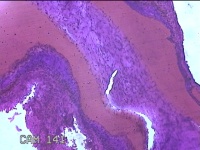

右侧肘后包块

性别

男

年龄

59岁

临床诊断

脂肪瘤

一般病史

发现右侧肘后包块1年余,无明显疼痛及不适。

标本名称

大体所见

灰白暗红色肿物1.3x0.5x0.3cm一个,表面糜烂。